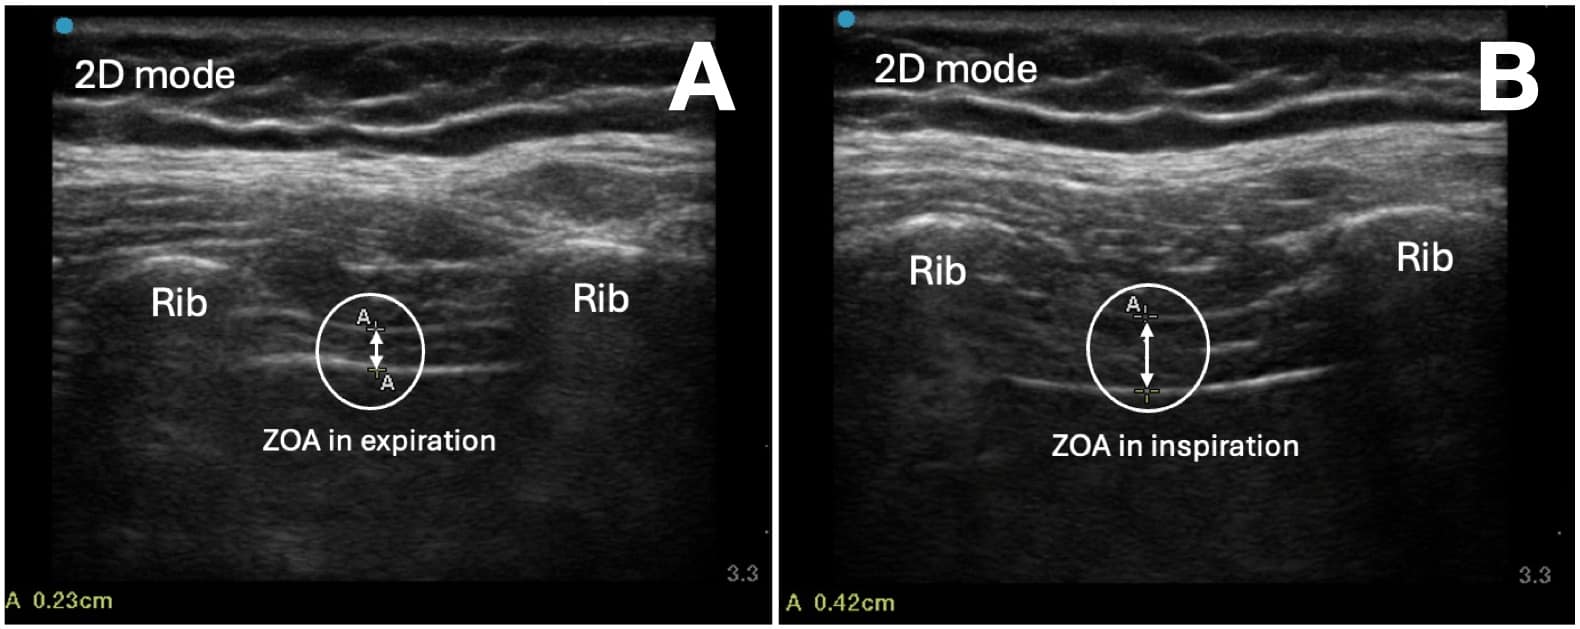

where Tdi is the maximum diaphragm thickness at end inhalation in the ZOA, Tde is the diaphragm thickness after passive exhalation in the ZOA, and TFd% is the diaphragm thickening fraction.

The measurement can be performed either with an M-mode scan or with two B-mode still images with calipers on each of the two images at end of deep inhalation and end exhalation, respectively (Figure 7). Most ultrasound machines will allow you to scroll through a saved loop and save still images. The transducer should be placed perpendicular to the thoracic cavity to ensure that the diaphragm borders are at their most echogenic and that the thickness is measured accurately. Rotating the transducer to be parallel with an intercostal space can limit diaphragm visualization, which may be obstructed by rib shadows.

In healthy subjects, the mean TF% during quiet breathing was 50.0% (SD=25.9) and 110.7% (SD=44.3) during deep breathing.26 During a maximal inspiratory effort, TF% typically ranges between 30% and 130%.27-29 In many cases, a visual assessment can demonstrate a thickening fraction of 100%, and in such cases, formal measurement and calculation may not be required. During quiet respiration, up to one-third of patients will have little or no thickening.29

Diaphragmatic paresis is present if the TF% is < 20%,20,27,28 and diaphragm atrophy is present if the Tdi is < 0.2cm.9,27 Diaphragm thickening analysis has a high sensitivity (93%) and specificity (100%) for diaphragmatic dysfunction30 along with a high intra-rater and inter-rater reliability.28 In patients that are mechanically ventilated, diaphragm thickening is an indicator of diaphragm effort and dysfunction.31 It has been used to predict extubation success in critically ill patients.32